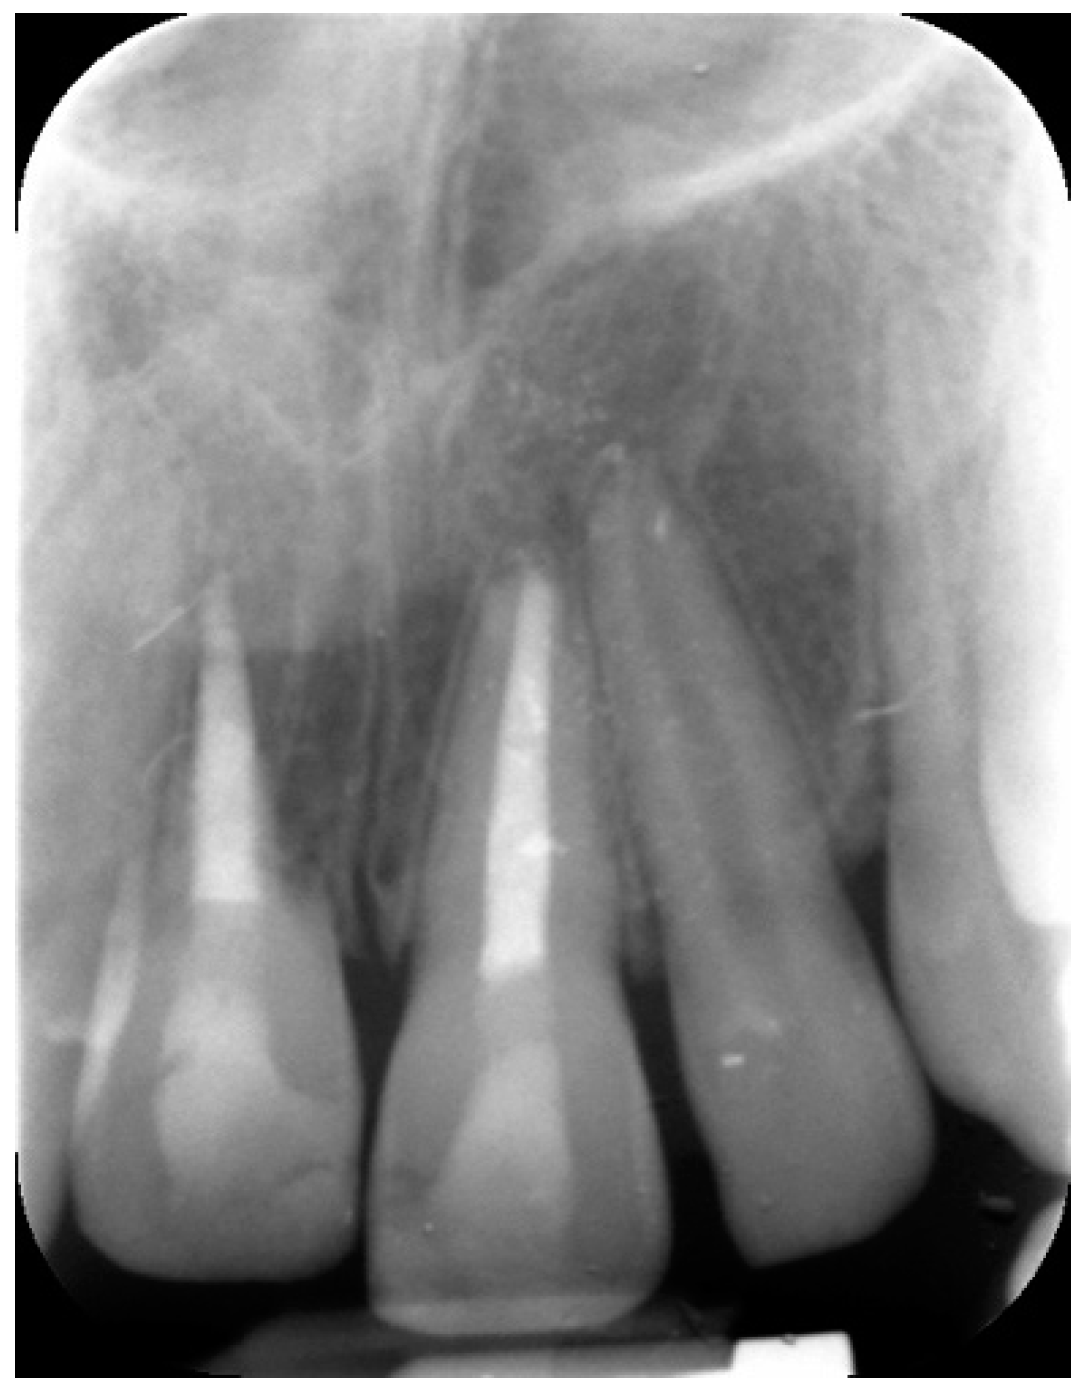

2. Case Report